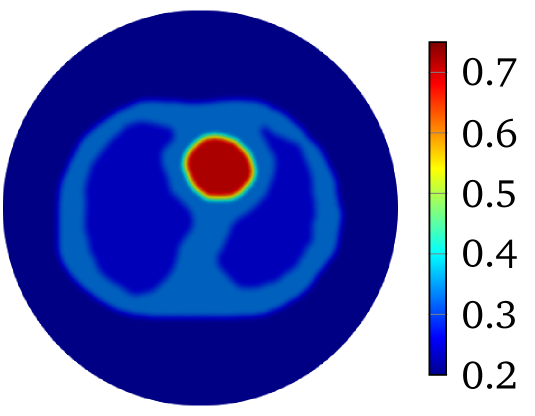

to produce with for 2D problem. The constant is selected so that . The value of is and for heart-lung model and human-brain model, respectively. The true smoothed distributions of for the two models are shown in Figure 2.